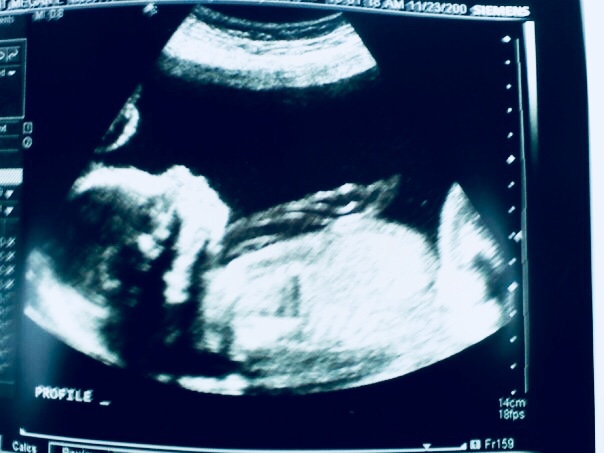

I was 6 weeks along. I had my first appointment on May 28, 2009; they confirmed my pregnancy. My due date was January 19, 2010.

I remember the doctor saying it would take a few months for my body to get back to normal, before we could begin trying to get pregnant again. So much to our surprise, just a short time later, we found out we were pregnant again.

Fast forward to my due date: April 1, 2010. Funny, huh? April Fool’s Day. Well, unlike my other children, this one came on his own without induction and pitocin. A week later than his due date, our amazing son was born, weighing 11 pounds 6 ounces. There’s a picture of me smiling between pushes, no idea that he would be so big, but overjoyed that we had made it.